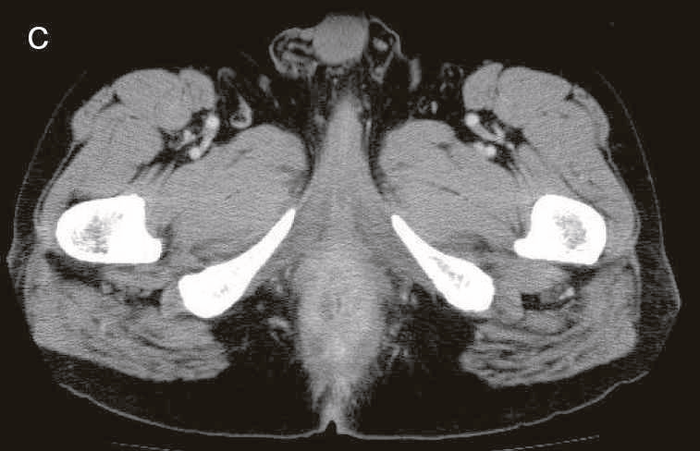

図43 腹部骨盤CT

CTではMRIと同様に広範囲のhigh density areaがあり,癌と炎症が波及した領域の区別がつかず右側方領域にリンパ節腫大を認めた。

図44 術式と術中所見(直腸切断術,リンパ節郭清(D3))

術中所見では,肝転移,腹膜播種はなく,腹腔内には転移を疑うリンパ節は認めなかった。

下腸間膜動脈を根部で処理するD3郭清と右側方リンパ節郭清を施行。術前画像にもあるように直腸間膜の肥厚が著しく,骨盤内からは後壁側は腫瘍の背側から肛門挙筋付近までの剝離が可能であったが,前側は精囊腺,前立腺と炎症,あるいは癌の境界が不明で,精囊腺の頭側までしか剝離ができなかった(赤矢印)。また,肛門側は痔瘻の2次口を含む瘻管,硬結をすべて切除するように皮膚切開を施行した。前後壁とも骨盤側と会陰側からの操作を繰り返しながら,腫瘤からのmarginを確保しながら切除することとなった。このため,精囊腺の一部と前立腺の一部を合併切除した。